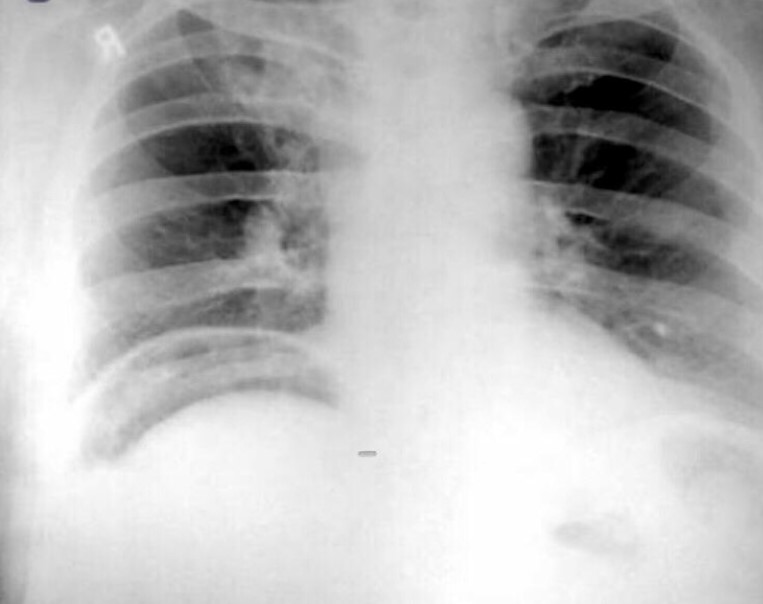

برای دیدن برنامه گروه جراحی اینجا کلیک کنید

.png)